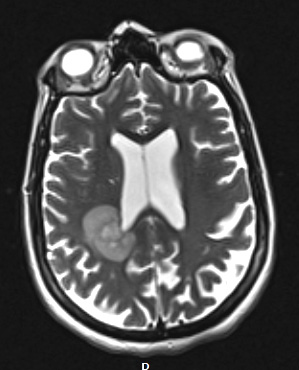

The lesion is present and somewhat irregular on this T2-weighted with contrast administration.